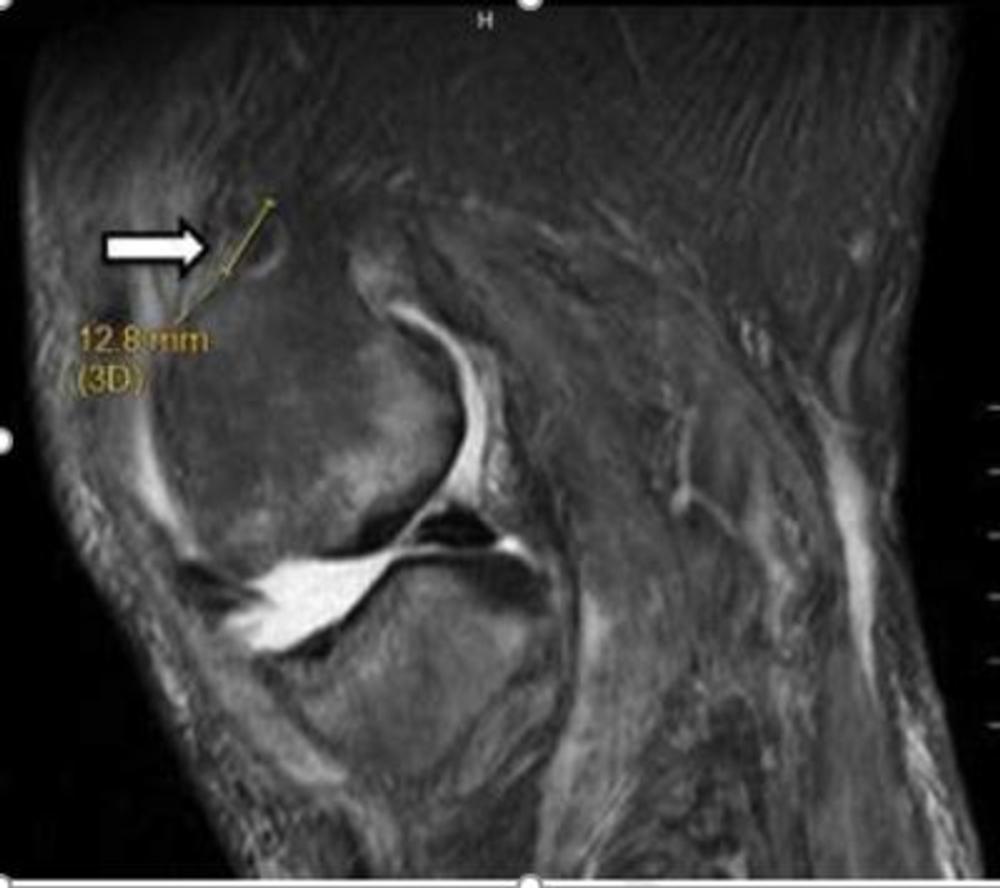

Figure 3. Image shows lesion produced by cooled radiofrequency neurotomy for chronic osteoarthritis knee pain.

Figure 4. Image shows lesion produced by cooled radiofrequency neurotomy for chronic osteoarthritis knee pain.